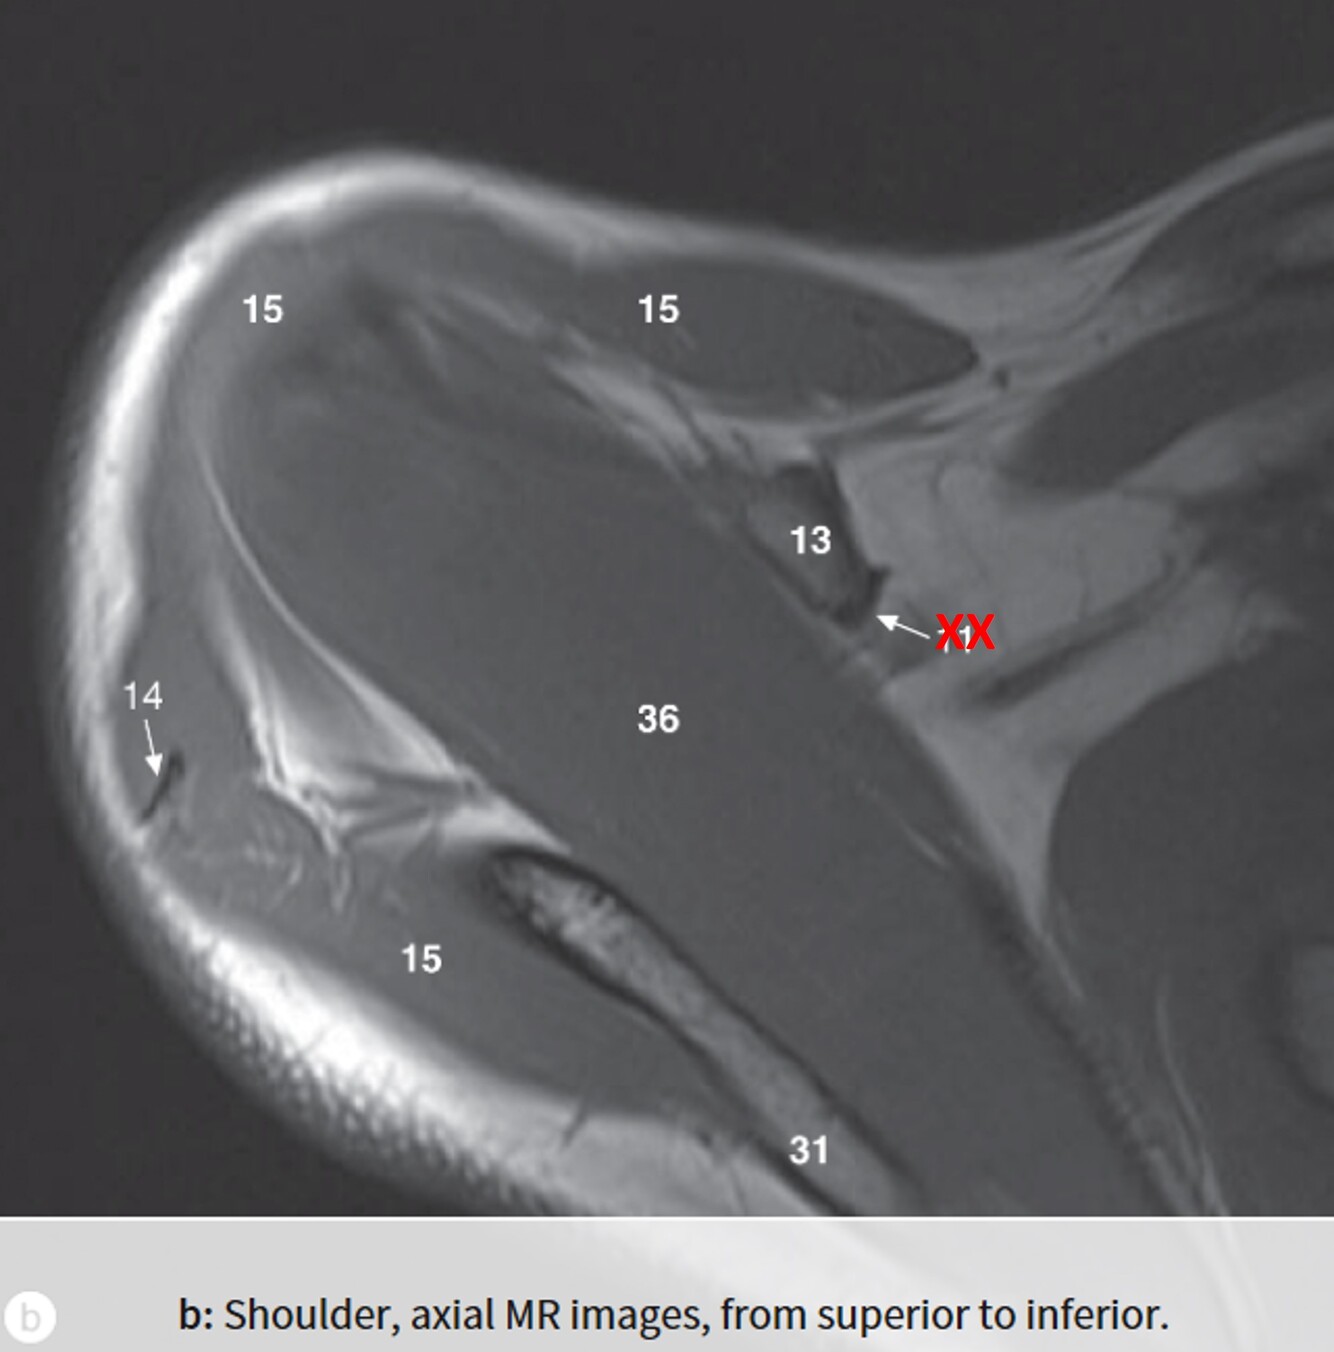

Label 31,13,15,36

A

31=Spine of rt. scapula

13=Coracoid process of right scapula

15=Rt. deltoid muscle

36=Rt. supraspinatus muscle